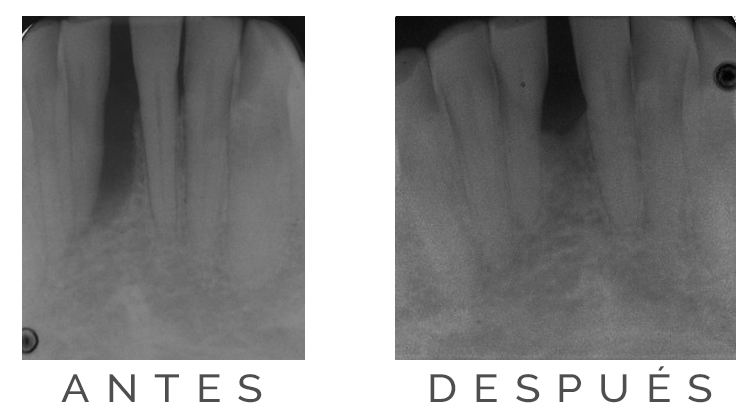

Tratamiento regenerativo En la radiografía 1 (antes del tratamiento regenerativo) se ve una gran pérdida de hueso alrededor del incisivo inferior (espacio oscuro alrededor de la raíz), provocando prácticamente la caída del diente. El paciente acude a nuestra consulta...